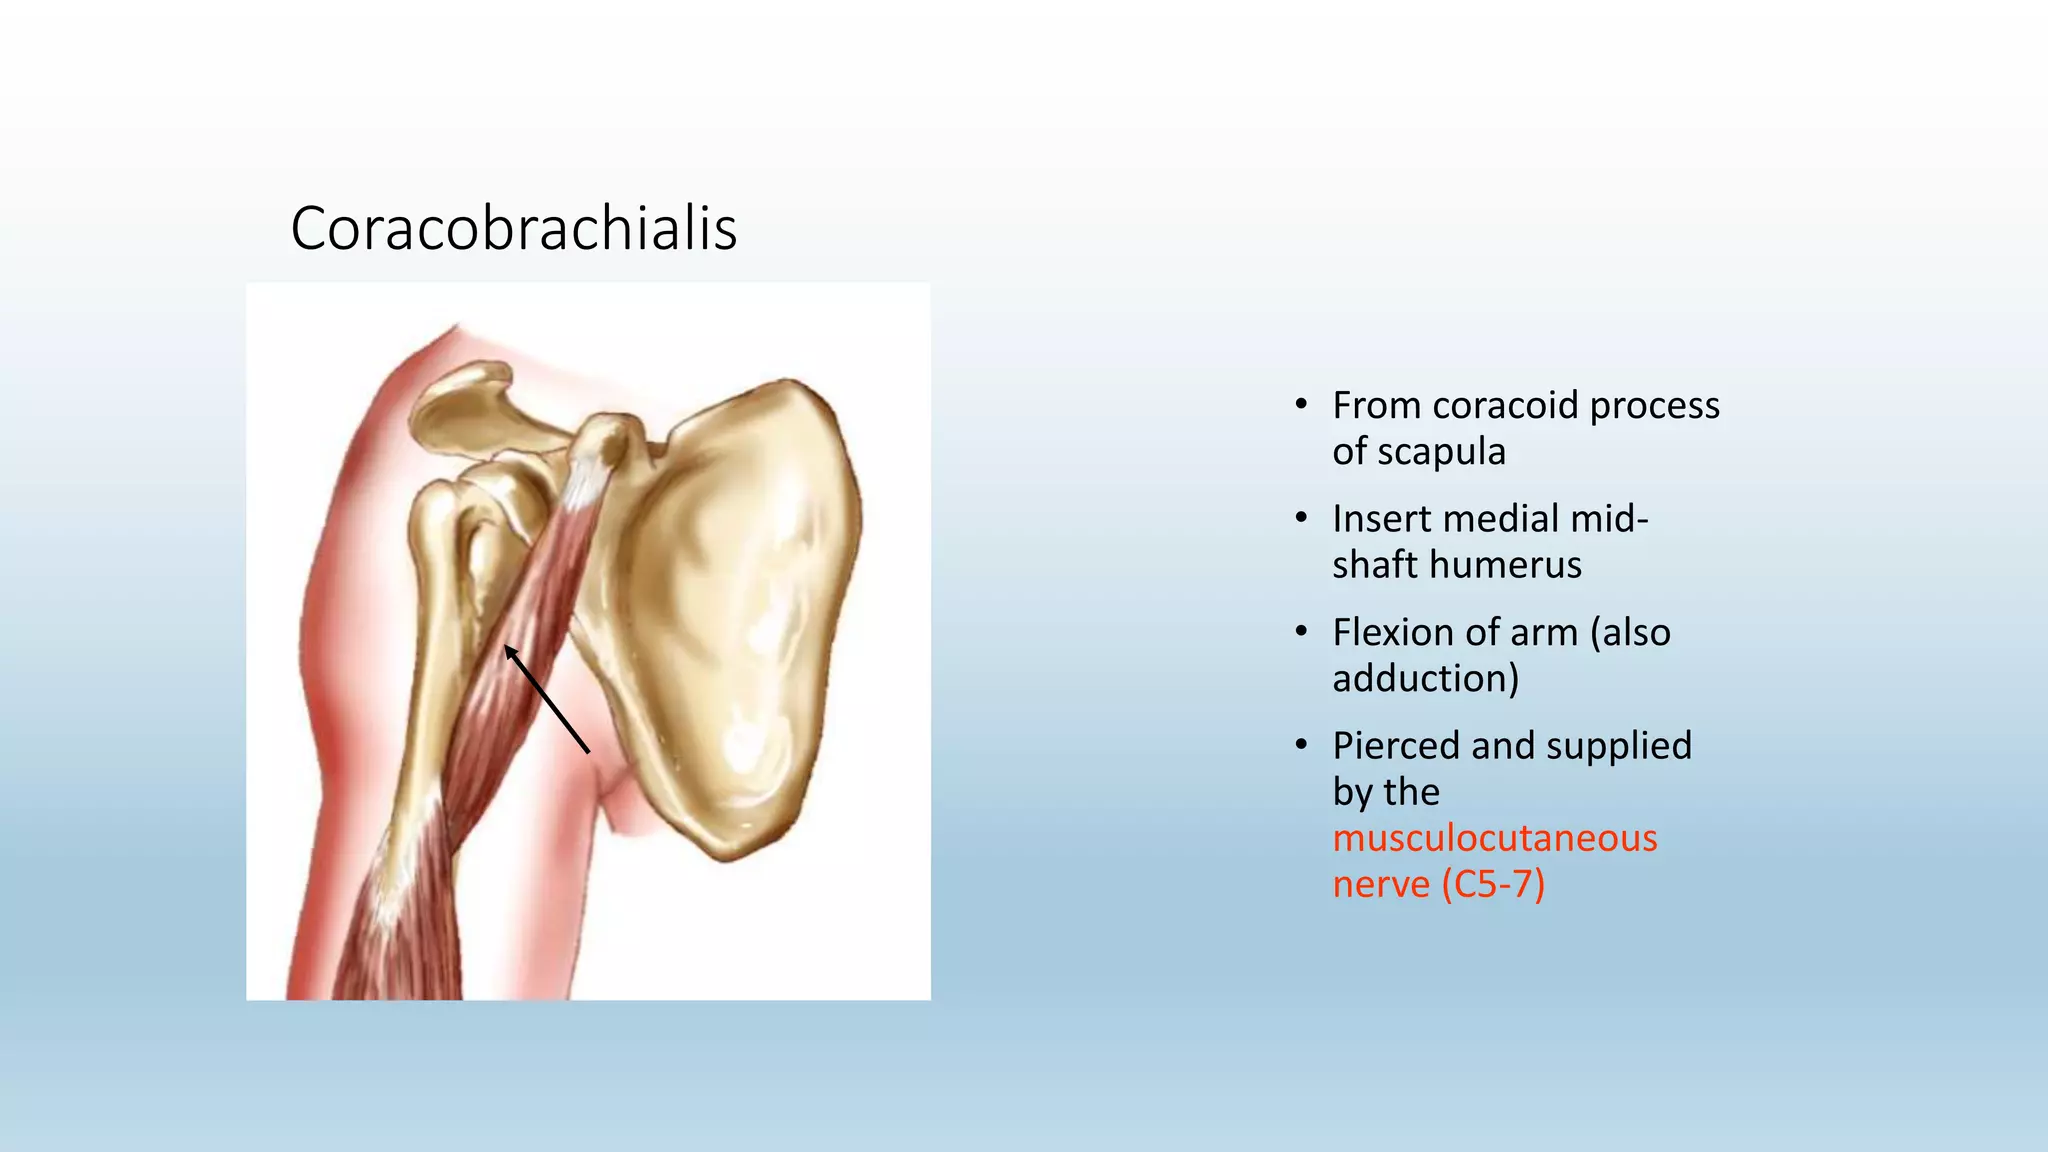

The document summarizes an anatomy revision session on the upper limb. It discusses various muscles of the upper limb including their origins, insertions, innervations and functions. Key muscles covered include the pectoralis major and minor, serratus anterior, deltoid, biceps brachii, brachialis, coracobrachialis, and triceps. It also discusses the rotator cuff muscles and muscles of the forearm including flexor carpi ulnaris and radialis. The session aims to help students identify upper limb muscles and understand their relations to nerves.